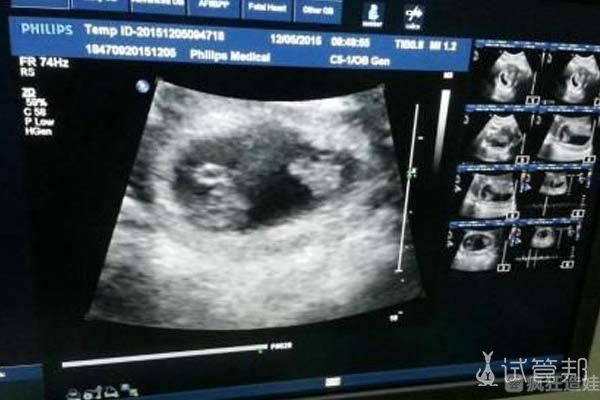

我是在第十二天的时候做的验孕,其实并没有抱多大的希望,在HCG是497.4这个检查结果出来之后,我真的是震惊又欣喜。在第七周左右的时候进行检查,医生说是两个胎心,这对我来说真的是意外之喜。